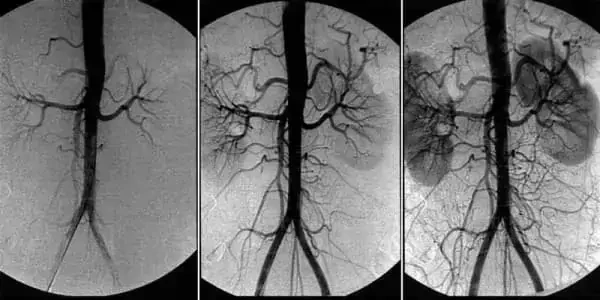

Многие годы вы можете не знать о своей болезни, не предъявлять жалоб, иметь высокую жизненную активность, хотя иногда могут случаться приступы «дурноты», выраженной слабости и головокружения. Но и тогда все полагают, что это от переутомления. Хотя именно в этот момент необходимо задуматься об артериальном давлении и его измерить. Гипертония может развиваться на протяжении многих лет, из-за этого ее называют «безмолвный убийца». Главным симптомом гипертонии является головная боль. Это происходит по причине сужения, спазма сосудов головного мозга.

Ангиодистония сосудов головного мозга – это патологическое состояние, при котором нарушается тонус сосудов и нормальное кровообращение в тканях головного мозга. В этой статье вы сможете прочитать про её причины, механизмы и симптомы, при которых пора бить тревогу. А также про грозные осложнения этого коварного заболевания и про современный подход к лечению, доступный каждому.

В основе лечения кровообращения сосудов головного мозга лежит очищение сосудов всего организма от накопленных загрязнений. Холестериновых бляшек, тромбов и кальциевой извести.

И чем больше загрязнений копится в сосудах, тем тяжелее будут последствия. При загрязнении сосудов головного мозга средней - средне тяжелой степени чаще всего случается инсульт и полная или частичная парализация.

Несчастные сосуды и так страдают от накопившихся «слоёв» холестерина, которые разъедают стенки эпителия, делают их тоньше. А сосудорасширяющие средства растягивают сосуды, создавая перенапряжение стенок. Если в такой момент сосуд не выдержит и лопнет, то случится инсульт.